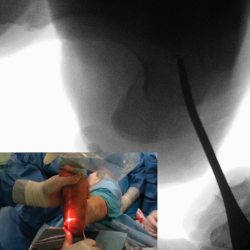

Se colocan fijaciones púbica y glútea con una almohada entre las extremidades para mantener horizontal la extremidad a intervenir. Se flexiona la rodilla contralateral para que no se vean imágenes fluoroscópicas superpuestas. Se coloca el fluoroscopio a espaldas del paciente (Figura 2).

Figura 2. Posición del paciente en decúbito lateral.

Figura 4. Imagen fluoroscópica de la fresa suelta introducida y su correspondencia en cirugía.

Ayudándose del mosquito para separar las partes blandas, se introduce una fresa Shannon 2 o 3 × 20 mm (FH Orthopedics, Mulhouse, Francia) en el vértice de la V. Comprobada la correcta posición de la fresa en la fluoroscopia (desconectando el motor de la fresa) (Figura 4), esta se avanza perpendicularmente al eje del calcáneo hasta atravesar la segunda cortical. Inclinando la fresa se pueden obtener diferentes desplazamientos, si bien, para conseguir un mayor desplazamiento, se recomienda avanzar perpendicularmente al eje. Si se quiere conseguir cierto efecto de descenso además de medialización de la tuberosidad se dirigiría la fresa en dirección de dorsolateral a plantomedial unos 15-30° respecto a la perpendicular del eje del calcáneo. Si lo que se quiere es obtener un efecto de elevación (beneficioso en el cavo posterior), la dirección sería la contraria, es decir, de lateroplantar a dorsomedial. Se podría obtener también acortamiento del calcáneo si la fresa se dirige de lateral distal a medial proximal, e incluso un alargamiento (de lateral proximal a medial distal), aunque esto último dificultaría el desplazamiento por la tensión de los tejidos(13).